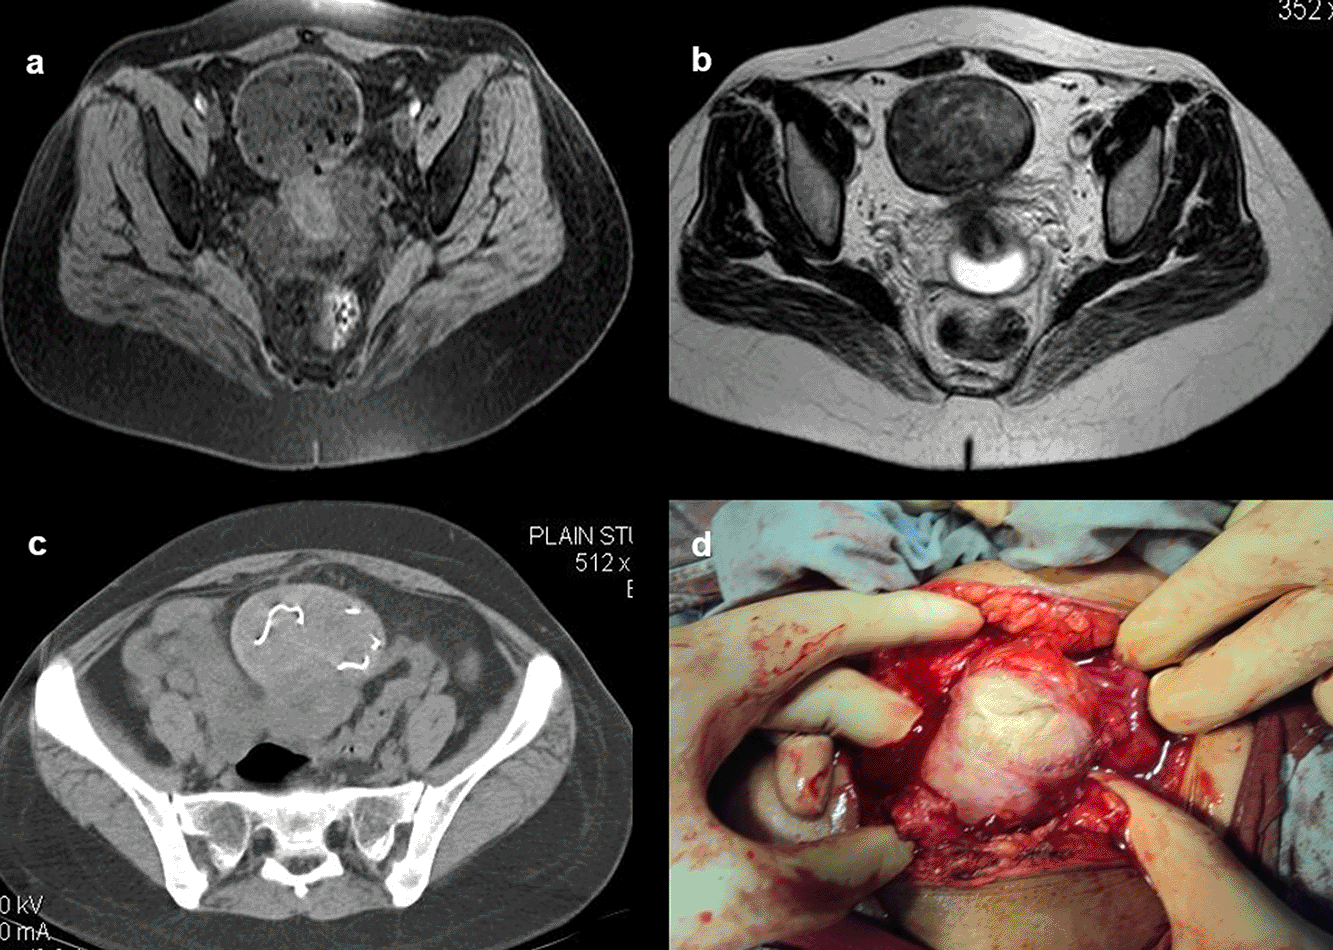

Case 10: A 33-year-old female came with a history of bleeding pervagina for six months. On palpation, the patient had tenderness with mild guarding in the hypogastric region. The rest of the clinical examination was non-contributory. MRI shows heterogeneous altered signal intensity soft tissue mass anterior to the uterus with multiple hypointense foci within. CT showed multiple linear metallic strings within a mass of soft tissue density anterior to the uterus, suggesting a foreign body (gossypiboma). The patient was operated on, and a large surgical sponge was removed.

After surgery, not infrequently, patients have surgical items inside their bodies. Surgical drains, wound gauze packs, bandages, skin staples, small surgical staples, intra-arterial, intravenous, intra-spinal, and intraabdominal catheters are among the postoperative supplies that are most frequently seen. Other uncommon materials, such as retained abdominal sponges (Figure 10a-d) and needles, that were unintentionally left behind after surgery, are challenging to find clinically and radiographically because patients have vague symptoms, these objects are difficult to see on radiographs, and the radiologist and referring physician have a low level of suspicion for such objects. The nursing staff may perform a comprehensive sponge count at the conclusion of a surgical procedure and identify any remaining surgical sponges right away. A misplaced sponge may not be identified for months or even years after surgery if it is not found at that time. The foreign body reaction to a surgical sponge left inside the body for a long time is frequently called a gossypiboma. The sponge’s cotton matrix is what creates the foreign body reaction’s nidus. There is the development of a foreign body granuloma with surrounding fibrosis and retraction around the cotton nidus. Many people have no symptoms, and the retained sponge is often only unintentionally found when the patient has a radiological examination for another reason.13–17